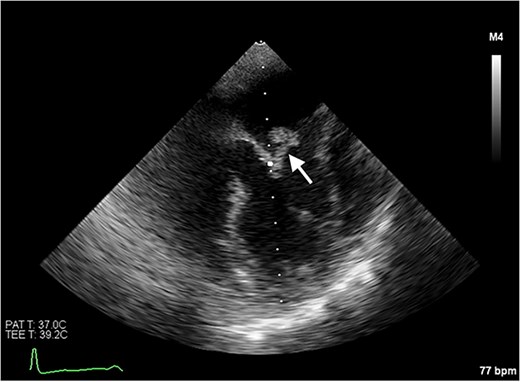

Echocardiography revealed a 1.2 cm pedunculated mass attached to the anterior mitral valve leaflet (AMVL) with severe mitral regurgitation (Fig. 1). Computed tomography imaging revealed multiple hepatic lesions (suspected septic emboli, Fig. 2), and a cavitating mass in the posterior aspect of the left upper lobe of the lung (Figs 3 and 4). Magnetic resonance imaging showed multiple cerebral lesions (Fig. 5), also thought to be septic emboli. Her presentation was suspected to be due to infective endocarditis rather than ischaemic, as troponin was negative, and coronary angiography was unremarkable. She was therefore treated promptly with intravenous vancomycin and gentamicin as per local antimicrobial guidelines. However, she failed to recover, and her case was reviewed in the regional in-house urgent cardiac surgical multidisciplinary team meeting. Considering her persistent fever, as well as the recurrent emboli, the decision was made to transfer her to our centre for emergency surgery.

Transoesophageal echocardiogram showing the pedunculated mass on the anterior mitral valve leaflet.